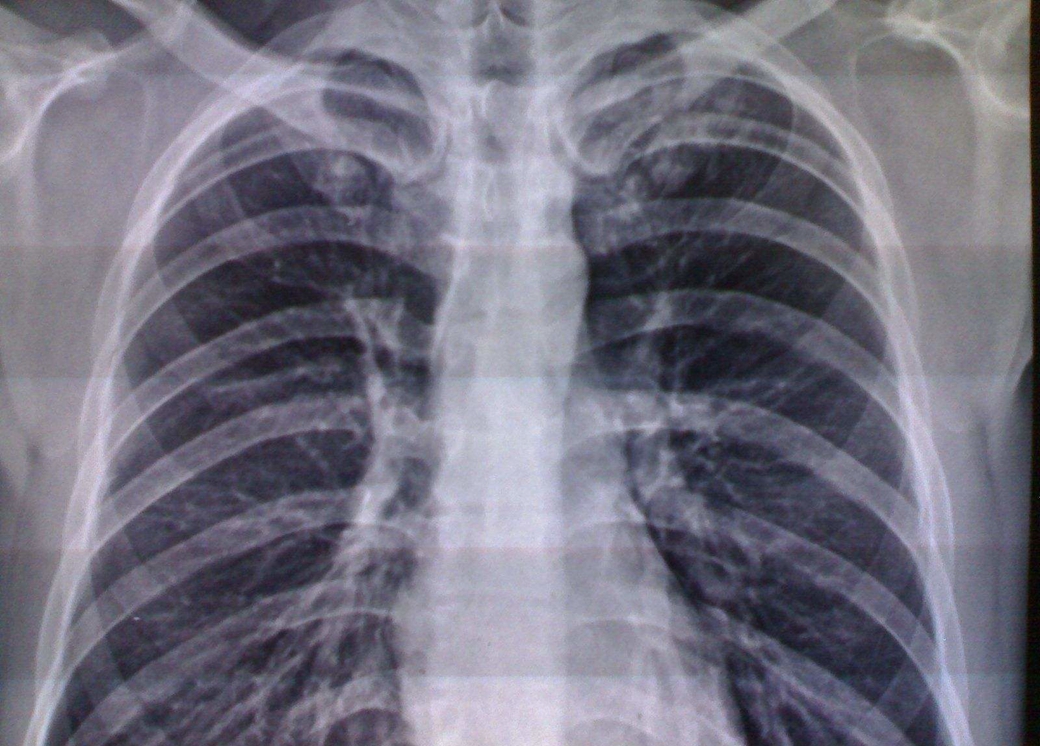

呼吸系統(tǒng)基本病變:滲出性病變,增殖性病變,腫塊性病變,空洞與空腔,纖維性病變,鈣化病變。

彌漫性阻塞性肺氣腫:①胸廓呈桶狀,前后徑增寬,肋走行變平,肋間隙增寬,橫膈較低平,膈活動度減弱。②兩肺野透明度見增加,呼、吸時其改變不大,可見單或多發(fā)肺大,肺紋理可見稀疏變細(xì),中外帶紋理可消失,肺門處肺紋理可增粗,伴有肺間質(zhì)纖維化時,肺紋理不減少而增強,并可呈網(wǎng)狀或蜂窩狀。③心景居中而狹長呈垂滴狀。